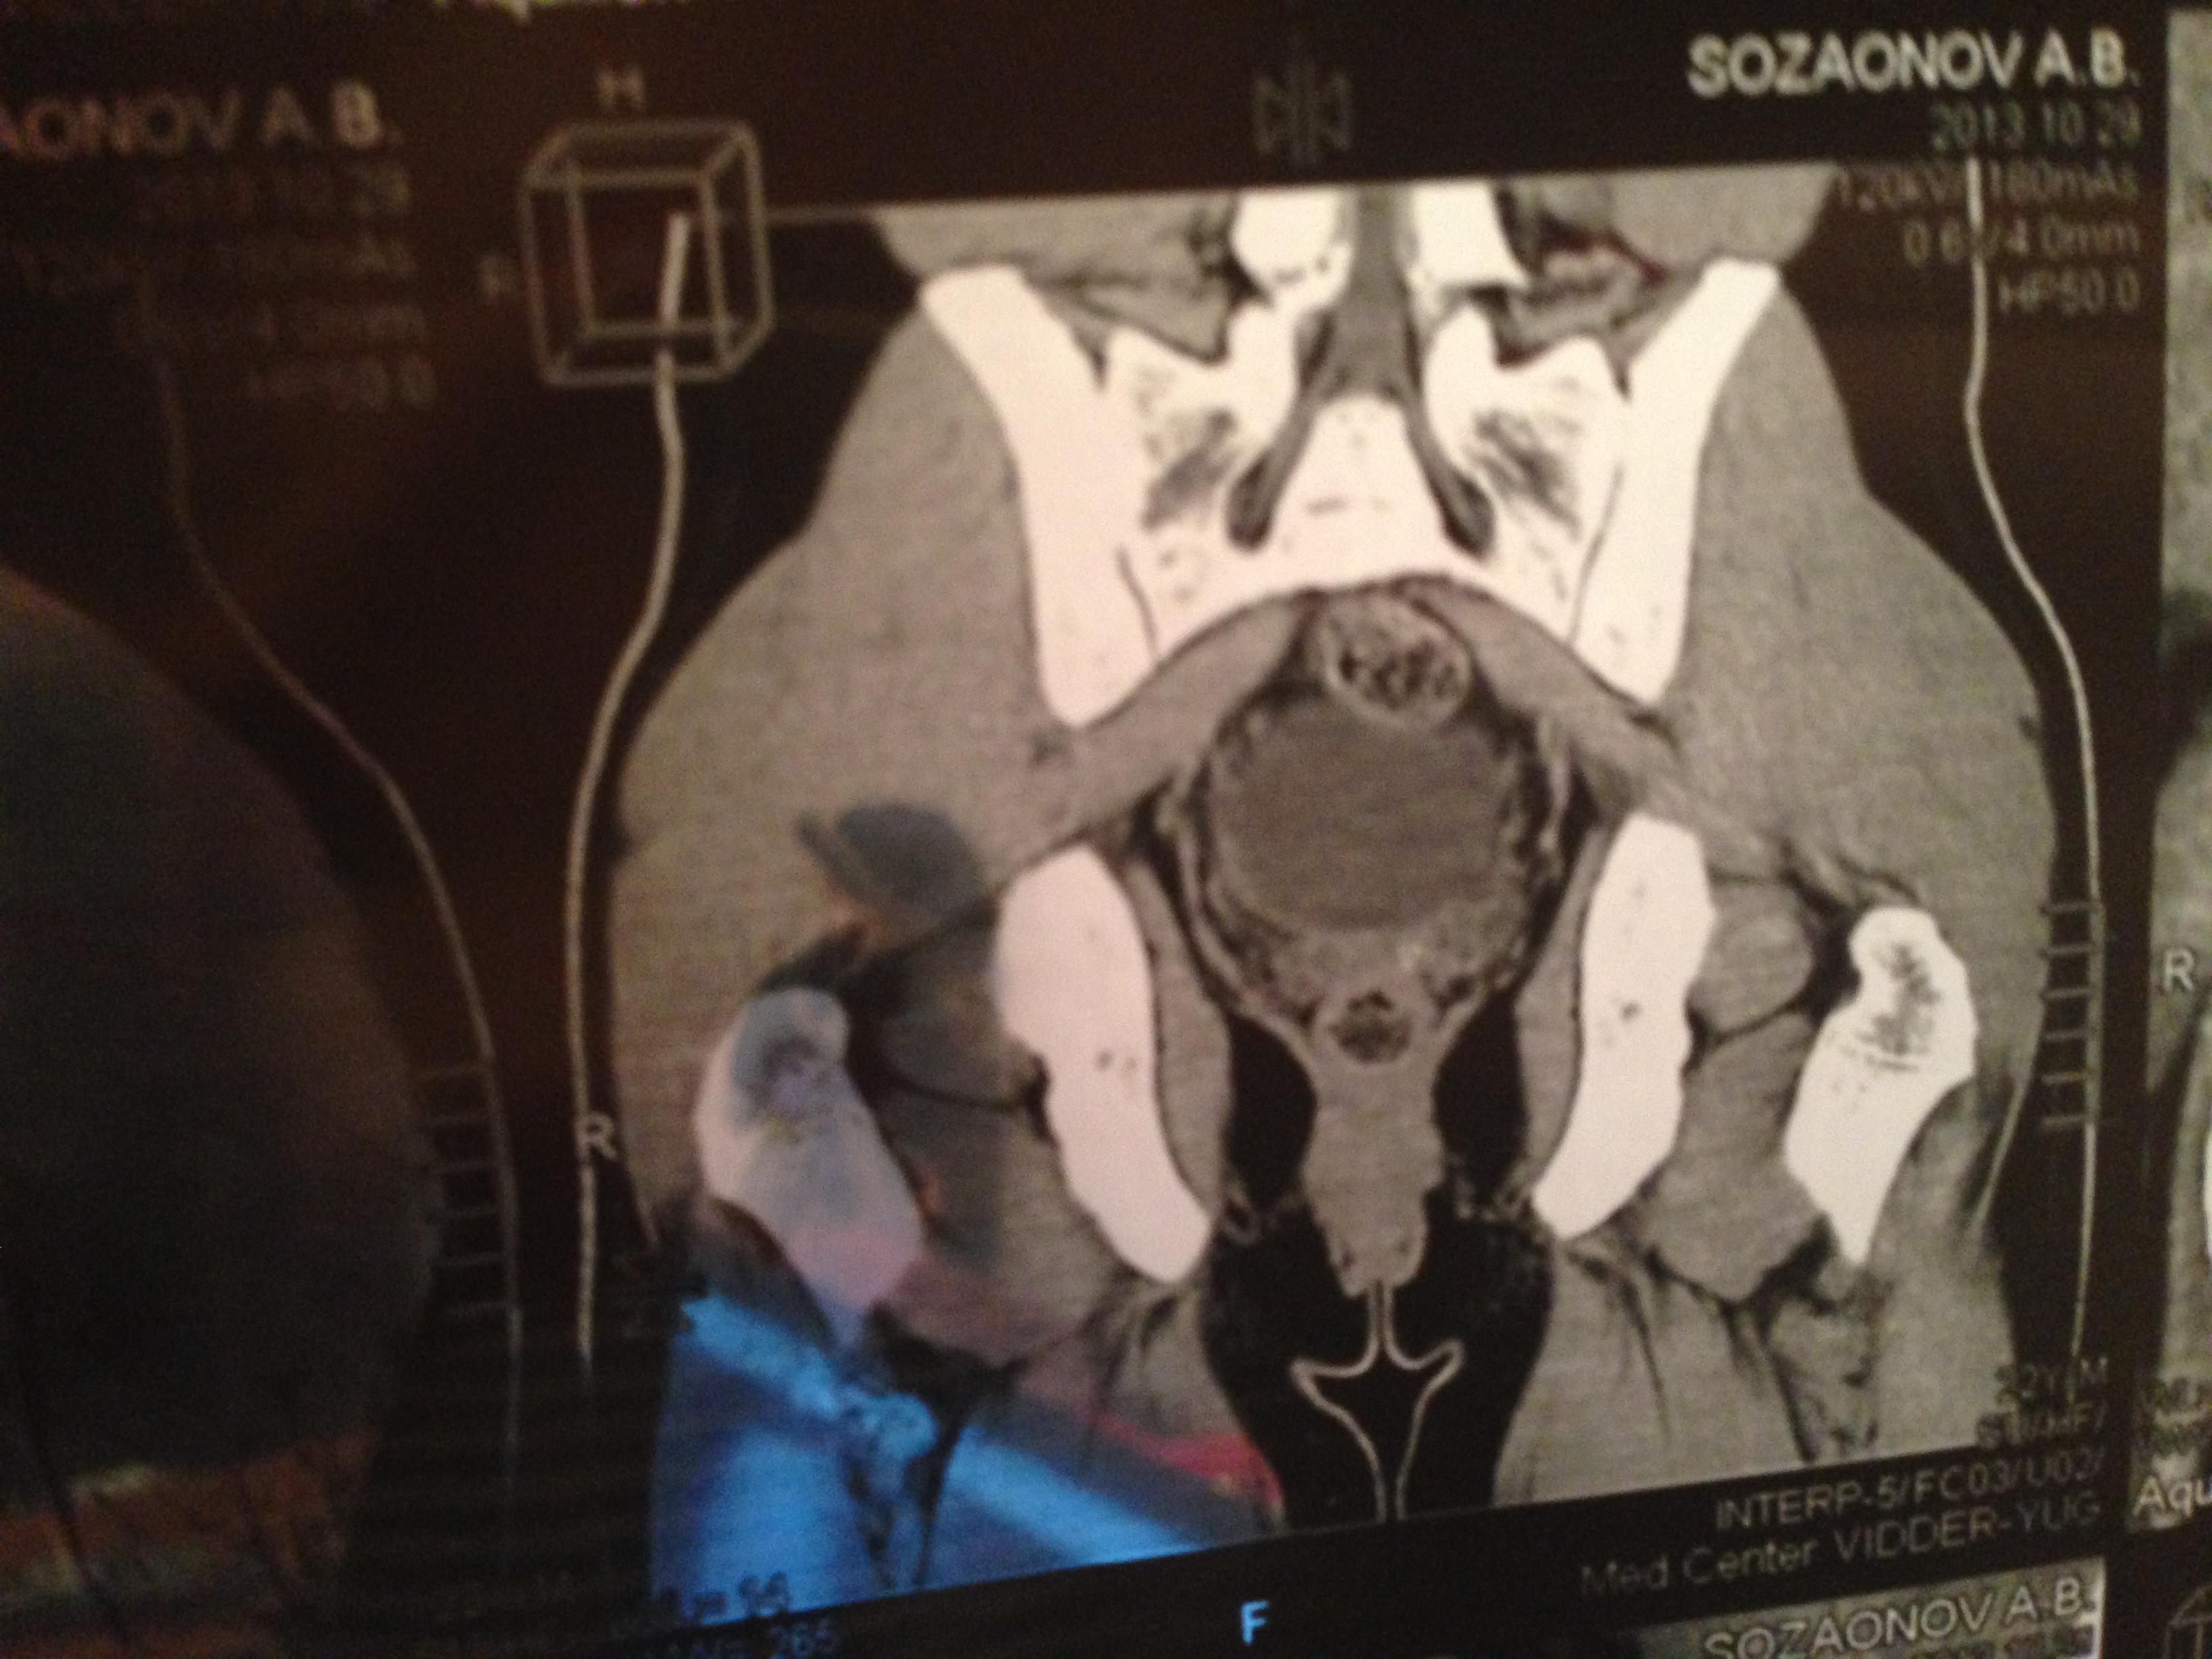

проведена МСКТ области таза!Внеорганных дополнительных патологических образований,лимфаденопатии или свободной жидкости в области таза не выявлено.

Мочевой пузырь-наполнен,стенки не утолщенны,паравезикально-без грубой органки.

Граница между предстательной железой и пузырем несколько четкая,контур пузыря на данном уровне не деформирован.

Предстательная железа-без грубой органики,еденичные микрокальцинаты.

Семенные пузырьки-конфигурация не совсем типична,примерный размер правого 26*28мм.Отмечаются признаки кистовидной трансформации и микрокальцинации обоих пузырьков.Наибольшая из кист слева достигает 9 мм.Обращает на себя внимание неравномерная кальцинация стенок крупных регионарных(текстикулярных)артерий с обоих сторон.

Костно-деструктивных изменений характерных для mts со стороны костей таза не отмечено.

Параректальная клетчатка-не изменена,патологически увеличенных лимфоузлов в параректальном пространстве не отмечено.M.m.levator ani-без особенностей.

Заключение:на момент исследования,КТ-данных за наличие внеорганных дополнительных патологических образований,лимфоденопатии или свободной жидкости в области таза не выявлено.КТ-признаки в пользу проявлений калькулезного везикулита с элементами кистовидной трансформации семенных пузырьков.